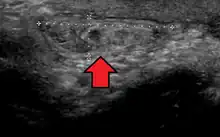

In the diagnosis of abdominal hernias, imaging is the principal means of detecting internal diaphragmatic and other nonpalpable or unsuspected hernias. Multidetector CT (MDCT) can show with precision the anatomic site of the hernia sac, the contents of the sac, and any complications. MDCT also offers clear detail of the abdominal wall allowing wall hernias to be identified accurately.[9]